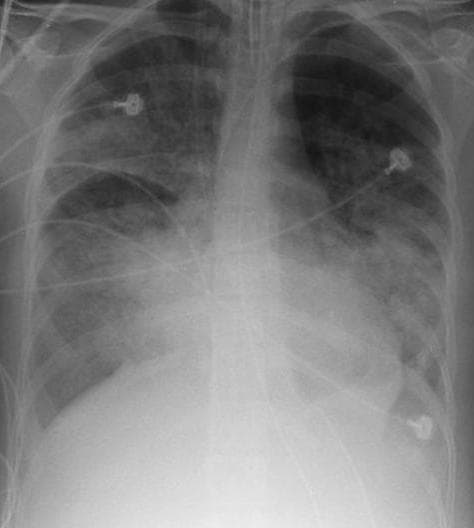

Le syndrome de détresse respiratoire aiguë (SDRA) est une cause de détresse respiratoire par œdème pulmonaire lésionnel. Le SDRA est défini par l'association de quatre critères : détresse respiratoire depuis moins d'une semaine, opacités pulmonaires bilatérales sur la radiographie thoracique ou la tomodensitométrie (TDM), pas d'argument pour une cause cardiaque d'œdème pulmonaire, et hypoxémie. Le SDRA est causé par une atteinte de la membrane alvéolocapillaire, dont la capacité d'échanges gazeux chute radicalement. Ceci entraîne également un défaut de compliance pulmonaire. Cette manifestation peut apparaître dans un grand nombre de situations pathologiques avec des mécanismes différents. Il est caractérisé par une inflammation du parenchyme pulmonaire qui mène à des anomalies d'échanges de gaz avec une libération en parallèle de médiateurs inflammatoires du parenchyme pulmonaire qui causent une inflammation et une hypoxémie. Souvent une défaillance multiviscérale résulte rapidement de cet état. Son traitement, à la fois étiologique et symptomatique, ne permet une survie que dans la moitié des cas pour les SDRA dits « sévères ». Son pronostic reste donc encore très sombre et il peut laisser des séquelles importantes. Le syndrome de détresse respiratoire aigüe a été décrit pour la première fois en 1967. LARDS Definition task force a proposé, en 2012, un ensemble de critères dits « de Berlin » afin de pallier les imprécisions des précédents critères diagnostiques (imprécision sur la définition du caractère aigu, absence de niveau de PEEP (positive end-expiratory pressure), chevauchements des notions dacute lung injury (ALI) et acute respiratory distress syndrome). Un SDRA est présent lorsque les quatre critères suivants sont présents : détresse respiratoire apparue depuis moins d'une semaine ; opacités pulmonaires bilatérales floconneuses sur la radiographie thoracique ou la TDM, non expliquées par un épanchement, une atélectasie, ou des nodules ; pas d'autre cause d'œdème pulmonaire, cardiaque, rénale ou hépatique, ni de surcharge volémique (échocardiographie nécessaire) ; hypoxémie avec un rapport PaO2/FiO2 < 300 mmHg.